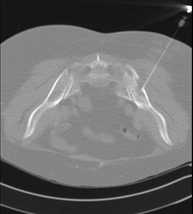

Exploració radiològica que mitjançant un sistema de raigs X i detectors que giren al voltant del pacient i que reconstrueixen les imatges per ordinador, permet l'estudi detallat de l'estern. - TC Clavícules

Exploració radiològica que mitjançant un sistema de raigs X i detectors que giren al voltant del pacient i que reconstrueixen les imatges per ordinador, permet l'estudi detallat de les clavícules. - TC Parrilla costal

Exploració radiològica que mitjançant un sistema de raigs X i detectors que giren al voltant del pacient i que reconstrueixen les imatges per ordinador, permet l'estudi detallat detalla de la Parrilla. - Angio- TC Cardíac o TC Cardíac